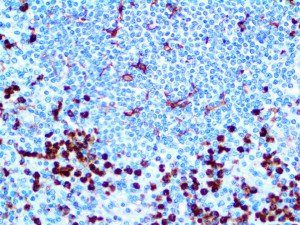

It is the ICU physician who is most likely to witness one of the deadliest manifestations of the abnormal immunological response, the cytokine storm syndrome (CSS). This response is also referred to by some as the cytokine release syndrome (CRS). CSS is characterized by continuous activation and expansion of macrophage and lymphocyte populations, which secrete large amounts of cytokines, causing the cytokine storm. This massive cytokine release is akin to hemophagocytic lymphohistiocytosis (HLH) disease, a syndrome characterized by initial unchecked and persistent activation of cytotoxic T lymphocytes and NK cells.

Clinical and laboratory manifestations of HLH include fever, enlarged liver and/or spleen, neurologic dysfunction, coagulopathy, liver dysfunction, cytopenias (i.e., low levels of erythrocytes, leukocytes, and/or platelets), hypertriglyceridemia, hyperferritinemia, hemophagocytosis, and eventually diminished NK cell activity as the immune system becomes progressively paralyzed. HLH can be familial (primary HLH) or secondary to another disease process (sHLH), such as rheumatic disease, in which it is referred to as macrophage activation syndrome (MAS, characterized by elevated ferritin).